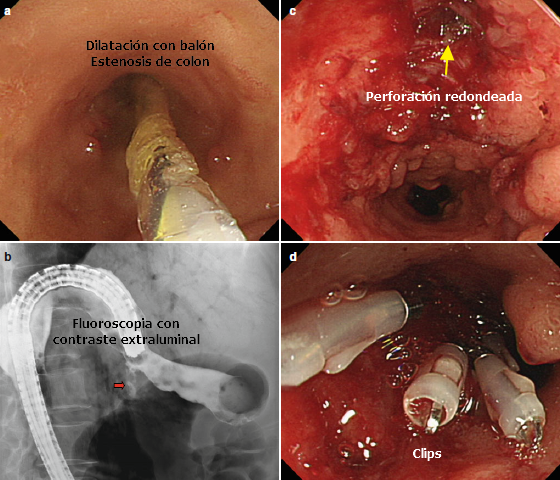

- Procedimientos de alto riesgo: la resección mucosal y submucosal endoscópica son procedimientos de riesgo elevado y depende del sitio donde se realiza. En el esofago la mayor experiencia se describe con la resección mucosal endoscópica para el tratamiento de Barrett asociado con neoplasia (riesgo de perforación entre 0-3%). La resección submucosa es la terapia de primera línea para pacientes con cancer de esofago epidermoide y pacientes con neoplasia y Barrett con características desfavorables para resección endoscópica mucosa (Tamaño del tumor mayor a 15 mm y con sospecha con infiltración submucosa (sm1)) Riesgo de perforación: 0-4%. La resección mucosal a nivel gástrico es un procedimiento seguro (Riesgo: 0.5%) en comparación con el riesgo en la reseccion submucosal(4%). la reseccion mucosal y submucosal a nivel duodenal implica un mayor riesgo comparada con los procedimientos en esofago y estomago. Las dilataciones son procedimientos que tienen un riesgo más elevado de perforación (2-3%), el riesgo es menor en patología benigna que en la maligna. también es mayor en estenosis complejas, secundaria a cáusticos y pacientes con acalasia.

- Para la perforación durante la resección submucosa y mucosal en el tracto gastrointestinal los endoclips son la terapia de elección. Si el orificio es muy grande la aplicación de clips en los extremos puede reducir el diámetro y hacer más factible la aproximación de los bordes. Si esto falla un endoclip con endoloop puede ser efectivo.

- Existen 2 tipos de Clips: los que se colocan a través del endoscopio y los que se colocan sobre el endoscopio (OTSC). Los clips convencionales se utilizan en perforaciones pequeñas (menores a 1 centímetro). Los OTSC son efectivos en defectos menores de 2 centímetros.